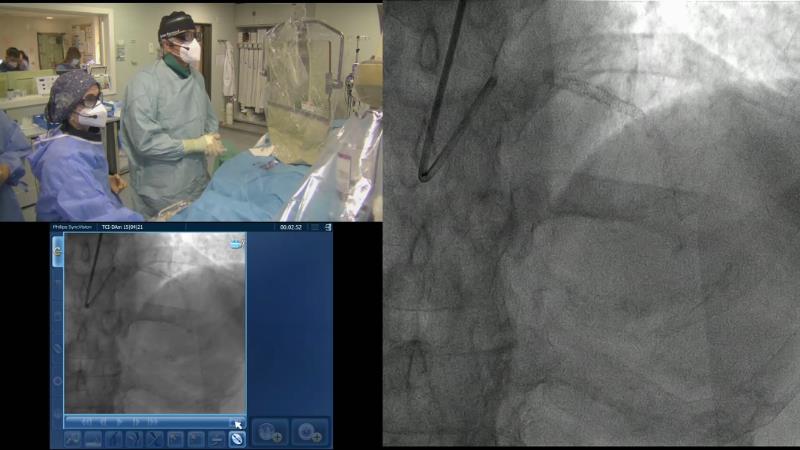

Follow the case study of this 70-year-old ex-smoker male patient with HTN, dyslipidemia, previous primary PCI to proximal and mid LAD because of anterolateral STEMI, presenting with syncope, and find out, through the debates around his treatment, how to use physiology in 2023.

- To learn how physiology pullbacks and angiography co-registration can help to define the patterns of atherosclerotic disease and guide treatment strategy

- To understand how to optimise PCI using physiology

- To learn key tips and tricks to obtain accurate physiological measurements